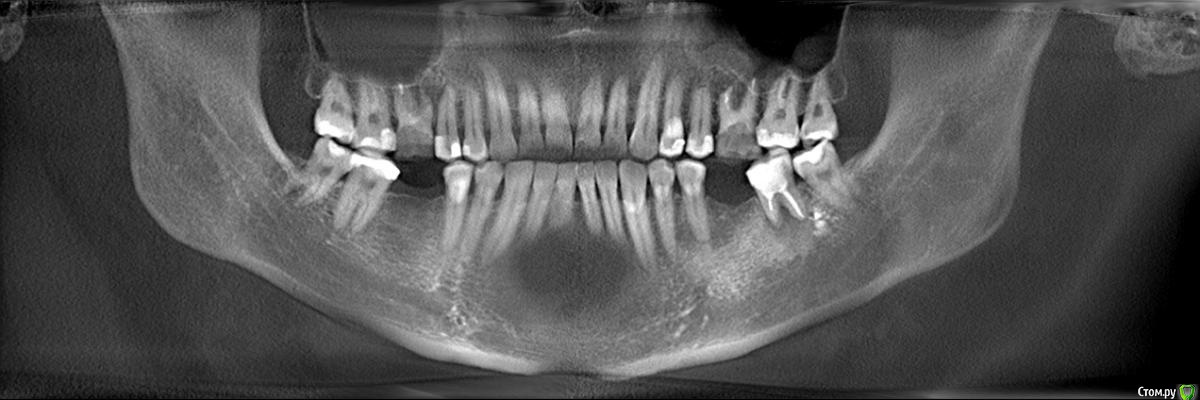

Faramir Опубликовано 18 апреля, 2019 Поделиться Опубликовано 18 апреля, 2019 (изменено) Сделал КТ. По 3D виду появился вопрос. Что это за разряжение кости в области шестерок на 3D виде КТ? Это нормально для КТ в этом месте или идет патологический процесс? Также интересно восстановится ли тут кость после удаления или лечения? Над левой шестеркой есть свищ над которым периодически вырастает и лопается белый шарик. Десна у правой шестерки за месяц дважды воспалялась, появлялась припухлость в виде валика, но после полосканий в течении 3 дней проходила. Можно ли спасти эти шестерки перелечив каналы или нужно удалять? У них в корнях стекловолоконные штифты на которые приклеены коронки/накладки наверное из керамики. Заранее спасибо за ответы. Изменено 18 апреля, 2019 пользователем Faramir Ссылка на комментарий